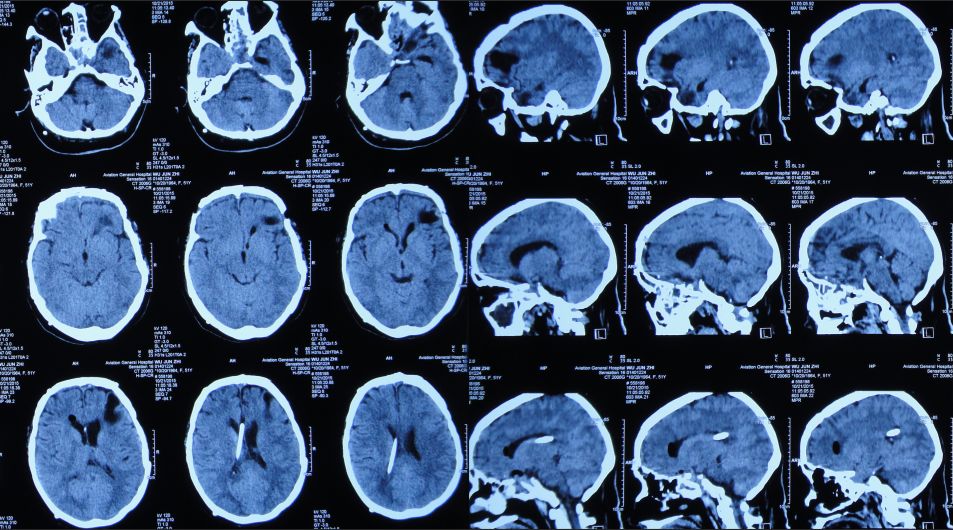

患者女,50岁,安徽省淮北市人。2014年12月14日,患者因高处坠落伤(2米左右)伤及头胸部及四肢,致昏迷,左耳、左鼻流血性液体,急诊前往安徽省淮南市潘集区某医院急查头CT显示左额叶脑挫伤、左侧颞骨凹陷性骨折、脑肿胀、颅内积气(图1);眼眶CT显示双侧眼眶内侧壁骨折(图2);胸部CT显示左侧肋骨骨折伴肺挫伤;右上肢X片显示右桡骨远端粉碎性骨折;左肩部X片显示左侧锁骨骨折。立即给予住院,保守治疗。

图1:2014年12月14日头CT:左额叶脑挫伤、左侧颞骨凹陷性骨折、脑肿胀、颅内积气